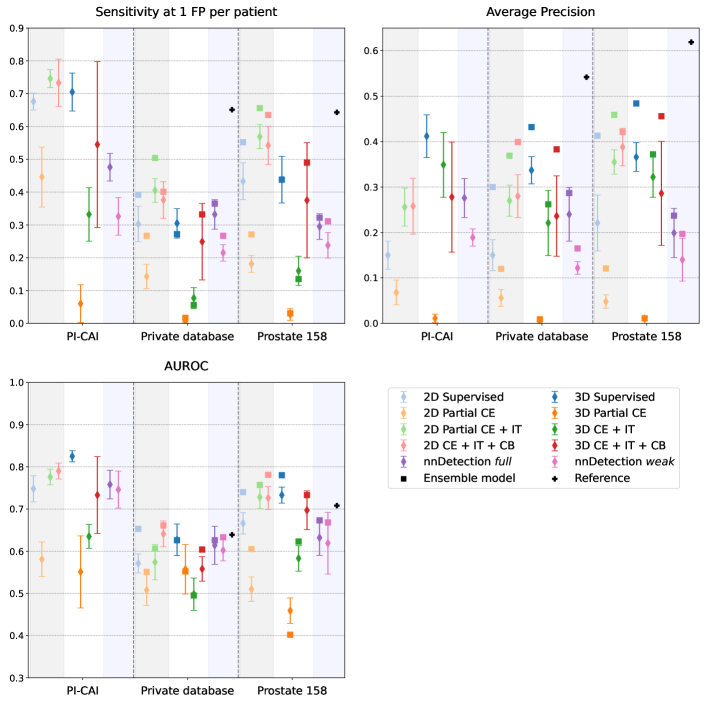

Figure 1 shows performance of all considered models for the three metrics of interest, namely sensitivity at 1 FP, AP and AUROC. Figure 3 provides examples of visual results of lesion detection maps for some 3D models. Extended visual results, including of 2D and ensemble models, are showcased in Appendix E.

First of all, it is important to note that the best performing model, namely the 3D supervised DynUNet, achieves a mean AUROC of 0.82 and mean AP of 0.42 thus producing a mean aggregated score of 0.62. This performance compares well against the best achievable reported metric on the PI-CAI challenge leader-board. We thus consider it a reliable baseline for our comparison. Surprisingly, the 3D supervised DynUNet is still outperformed by 2D models in term of sensitivity at 1 FP, including by models trained with weak labels.

The two weak models with size constraints (CE+IT, CE+IT+CB) clearly outperform the model trained only with partial and negative cross entropies (Partial CE), showing the interest of the additional size constraint cost functions. Between the image tag (IT) and the common bounds (CB) losses, the latter achieves a higher score in 22 of the 30 configurations. We use the term configuration to refer to a pairwise comparison between models with the same spatial dimension input (2D or 3D) and type of model (ensemble or not) evaluated on a given dataset and for a given metric. For instance, AUROC comparison between 2D CE+IT and 2D CE+IT+CB on Prostate158 accounts for one configuration. Remarkably, the models that have been trained with weak labels can outperform fully supervised models. They also perform favorably compared to nnDetection in most cases. The weakly supervised CE+IT+CB model achieves better scores than its supervised counterpart in almost all 2D configurations, but only 2 times out of 30 in 3D.

For almost all models, metrics and datasets, model ensembling improves the generalization performances, with a mean improvement of 20% among all models and metrics. We can note that for sensitivity at 1FP and AUROC, some models, especially with ensemble predictions, equal or surpass the reference metrics, which is the mean performance over 5 folds of the 3D fully supervised DynUNet trained and tested on the Prostate158 or private datasets, respectively. However, these reference models remain better in terms of AP.